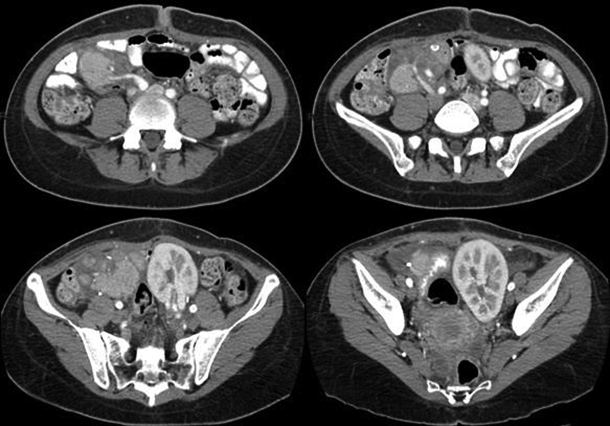

Fig. 8. TC post operatoria, un mes posterior a la cirugía.

En la segunda tomografía control efectuada se evidenció una disminución en el calibre de la anastomosis arterial, lo que se correlacionó con vasculitis. Con posterioridad a las complicaciones descritas, el paciente presentó los siguientes niveles de laboratorio: glucemia de 88 mg/dl y creatinina de 1.34 mg/dl.